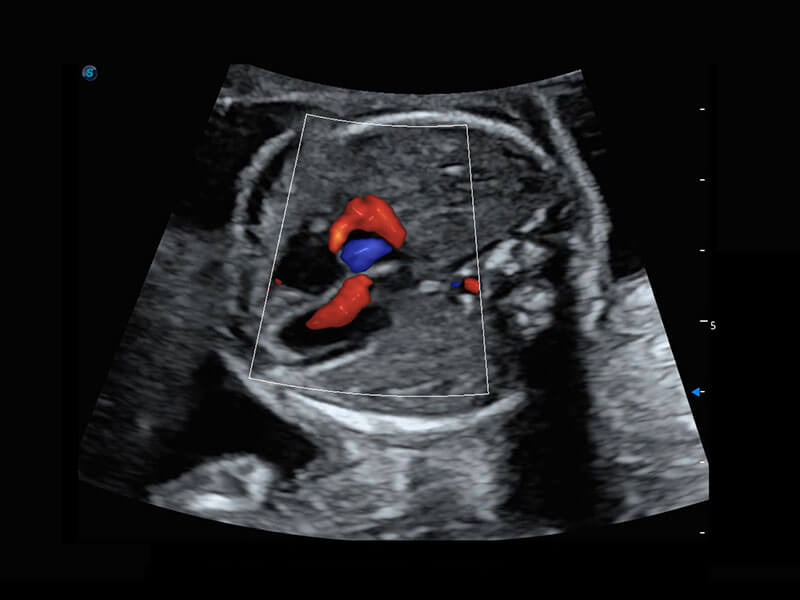

P60搭载一系列胎儿心脏成像技术,实现精细的胎儿心脏评估。

右室双出口

胎心容积成像